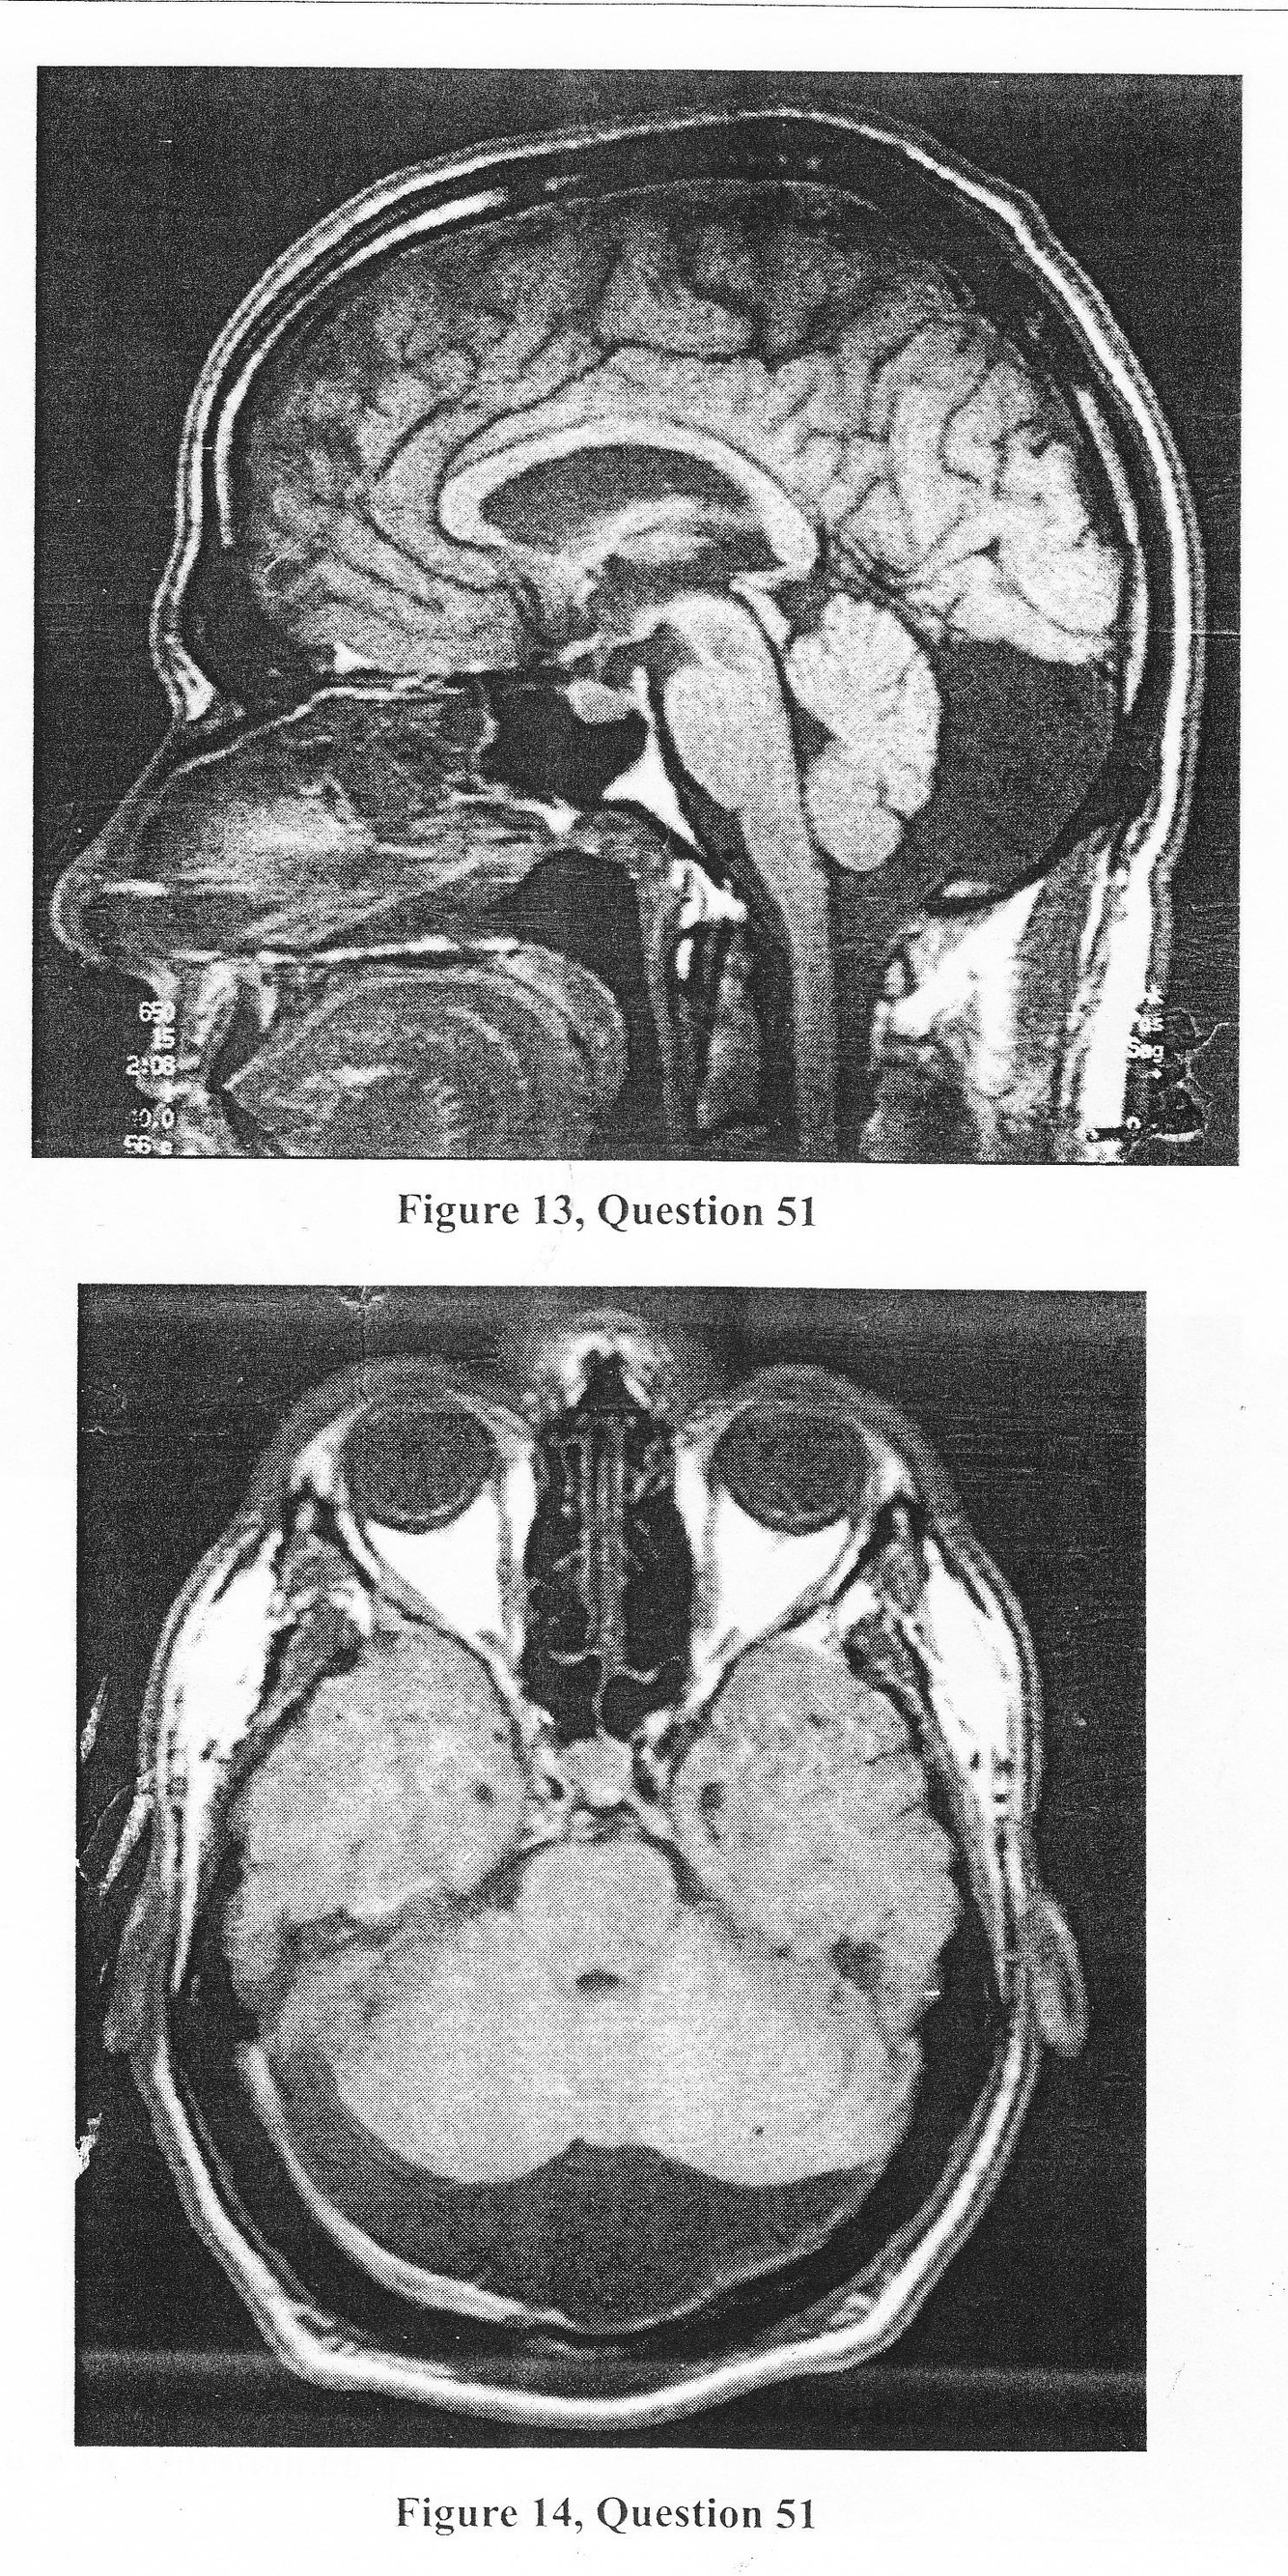

A.The differential diagnosis includes a mega cisternal cavity, retrocerebellar intra-arachnoid cyst, a Dandy- Walker malformation, and a Blake’s pouch.

B. The differential diagnosis includes a mega cisternal cavity and retrocerebellar intra-arachnoid cyst.

C. The MRI only depicts a mega cisternal cavity.

D. The MRI shows thinning of the occipital bone and deformation of the cerebellum.

E. Cisternography is not indicated.

A. ventriculoperitoneal shunt

B. resection of the posterior wall of the cyst, if defined by cisternography

C. cystoperitoneal shunt -

D.whatever the surgical therapy, patients typically improve following decompression of the posterior fossa space